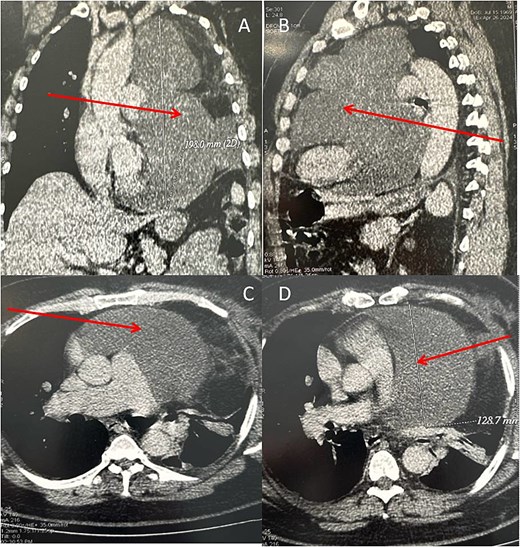

Because of the patient’s very poor echogenicity, TTE was unable to provide useful information, unlike thoracic computed tomography (CT), which revealed a mass of fluid density and homogeneous content, developed in the left pericardium and measuring 185 mm in height, 120 mm in transverse diameter and 140 mm in antero-posterior diameter. This mass compressed the left lung, which was reduced in volume, and displaced the heart chambers to the right (Fig. 2).

Chest CT scan (A: coronal section, B: sagittal section, C and D: axial section) in spiral mode with injection of contrast agent showing a giant pericardial mass (arrows).